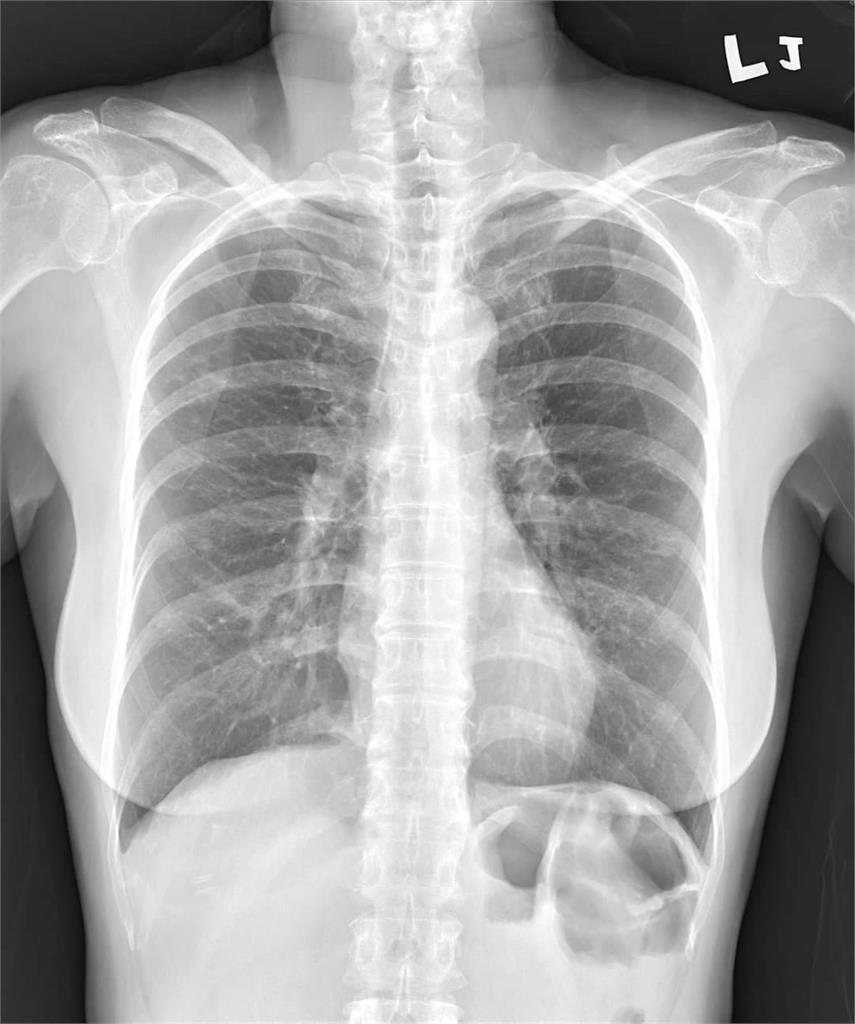

根據《ETtoday》報導,陽明醫院胸腔科醫師蘇一峰透過社群平台分享個案,日前收治一名50歲女病患,她本身有氣喘,平時症狀都相當穩定,不料最近突然發病,就診時直言:「咳嗽咳到要死!」照了X光發現她有輕微浸潤肺炎,照出一片白,但做了流感、新冠、黴漿菌等呼吸道病毒細菌的篩檢,卻全都是陰性,詢問平常作息才知道,罪魁禍首恐怕是家中鍋具。